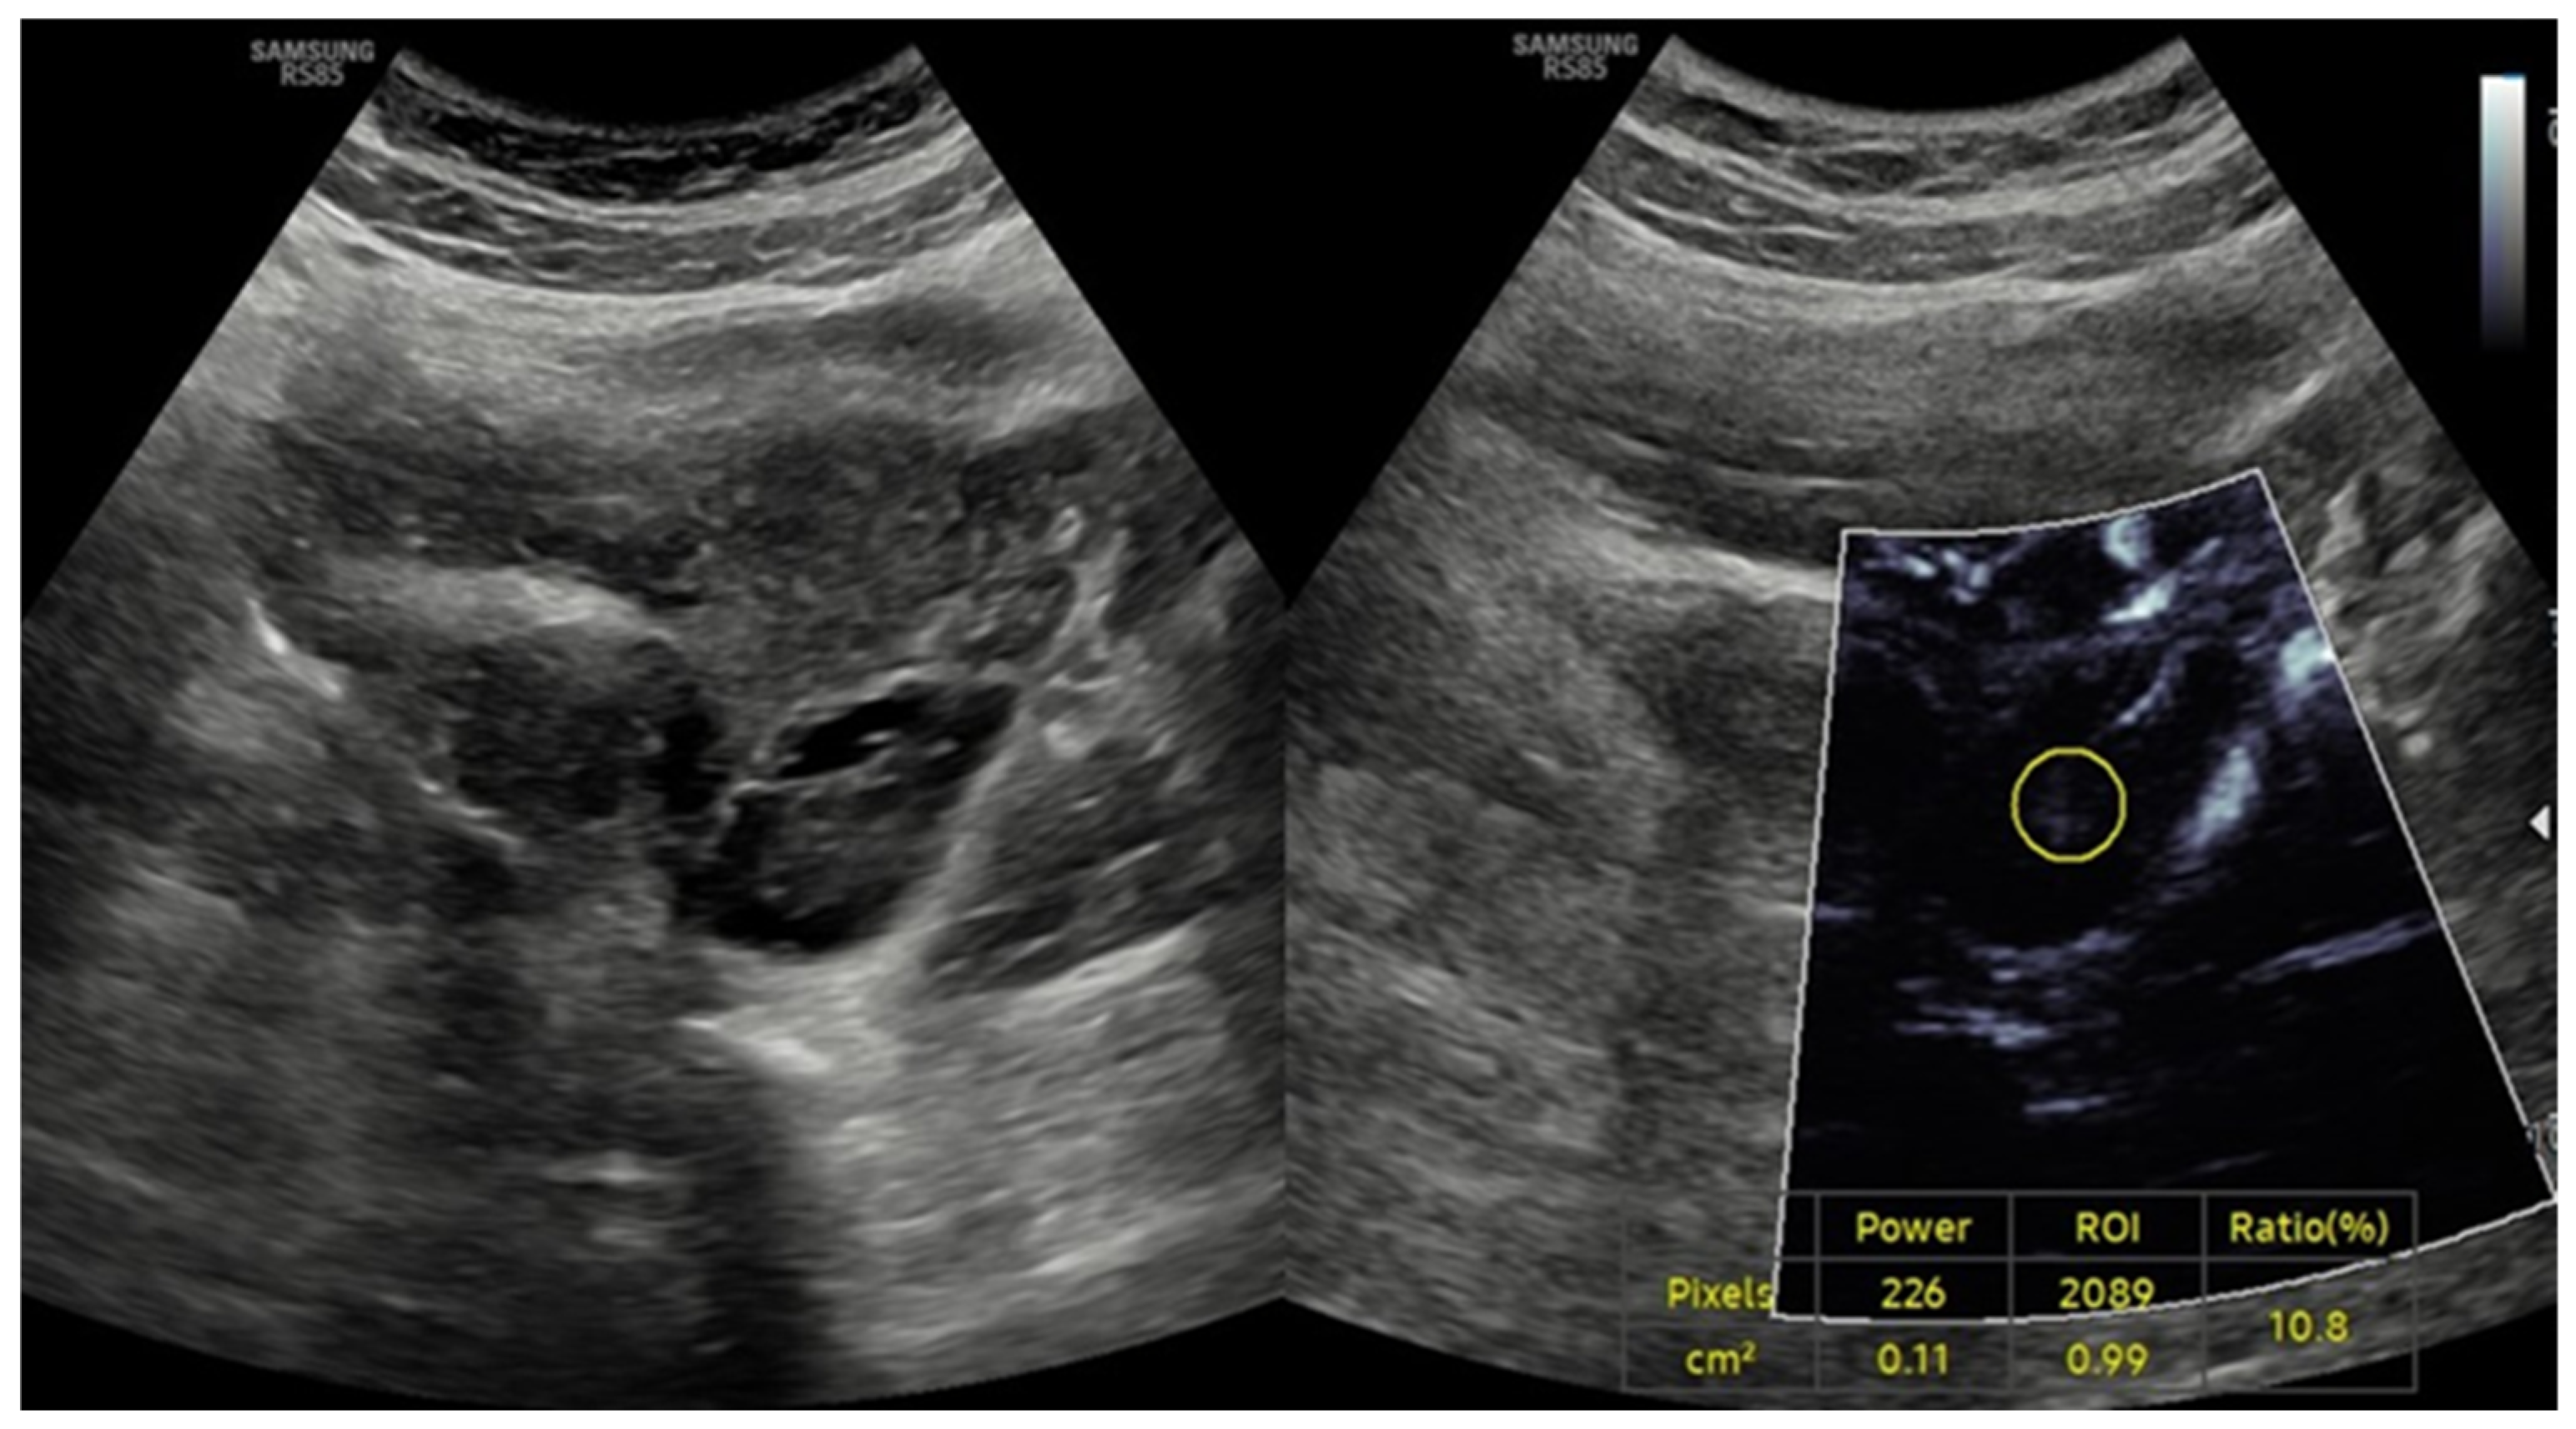

- Doppler Examination (MV-Flow, MVI): Ovarian stromal vascularity was evaluated using the same ultrasound equipment and transducer (Samsung RS85 Prestige with CA1-7A, 1–7 MHz). MV-Flow Doppler imaging was performed consistently in the longitudinal plane to maintain anatomical standardization. Cine-loop clips of at least 3 s duration were captured and stored. For vascularity index measurements, the optimal frame demonstrating clear vascular flow was selected from the stored cine-loop clips. In the ovarian stroma, three circular regions of interest (ROIs) were centrally positioned. These ROIs, each with a fixed 5 mm diameter, were carefully selected to exclude dominant follicles and peripheral vascular structures. The ROI dimensions and MV-Flow Doppler imaging parameters, including pulse repetition frequency (PRF), gain, and wall filter, were maintained consistently throughout the duration of the study.